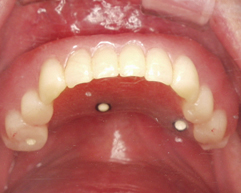

手術後

インプラントを5本入れ当日に仮歯を入れました。仮歯に穴をあけスクリューでインプラント体と固定します。こうすることにより動かない仮歯が作れます。